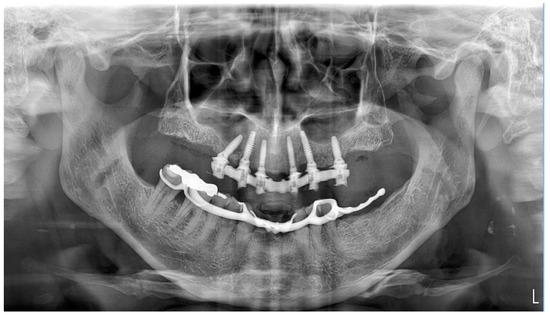

- 16: Oxy Implant FIXO Short 30° 4 × 10 mm

- 14: Oxy Implant FIXO Short 17° 4 × 10 mm

- 12: Oxy Implant FIXO Mini 17° 3.5 × 11.5 mm

- 22: Oxy Implant FIXO Mini 17° 3.5 × 13 mm

- 24: Oxy Implant FIXO Short 17° 4 × 11.5 mm

- 26: Oxy Implant FIXO Short 17° 4 × 8.5 mm